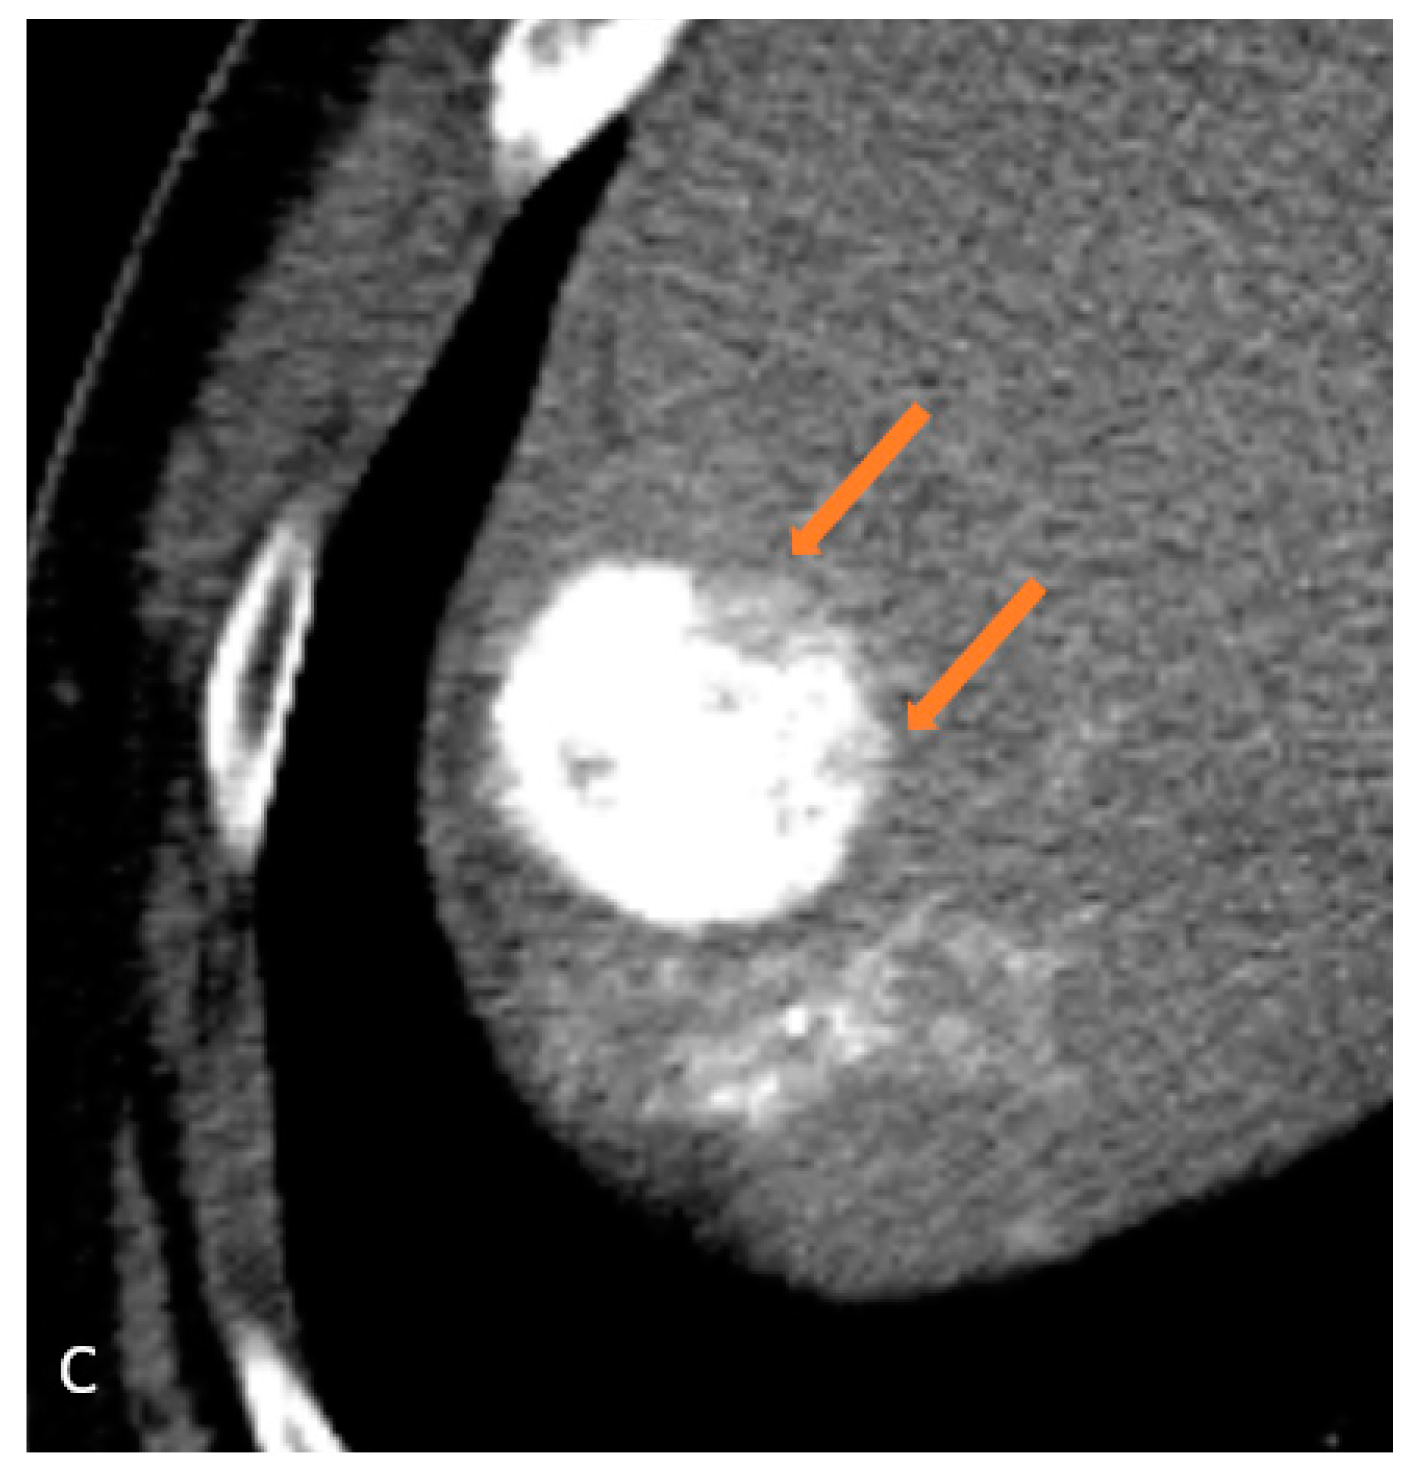

| 6 | CEUS | Target | LR-viable | CT missed subtle disease at the periphery of the treated HCC (Figure 2) |